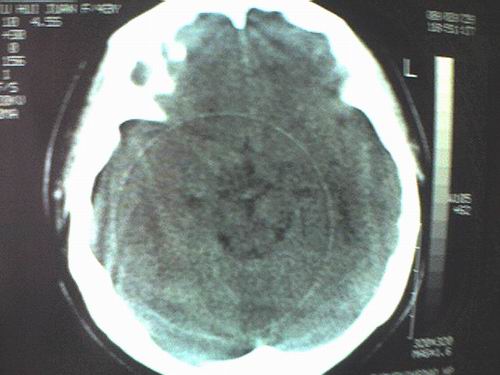

标题: CT12572:女 43岁 头痛恶心呕吐两天请求会诊 [打印本页]

女 43岁 头痛恶心呕吐两天

手机照的,不是太清楚。

右侧大脑镰硬膜下出血

1、右侧大脑镰硬膜下出血2、机器伪影太重,该修修。

右侧大脑镰旁硬膜下血肿;如此重的机器伪影,要小心了,快报修吧!